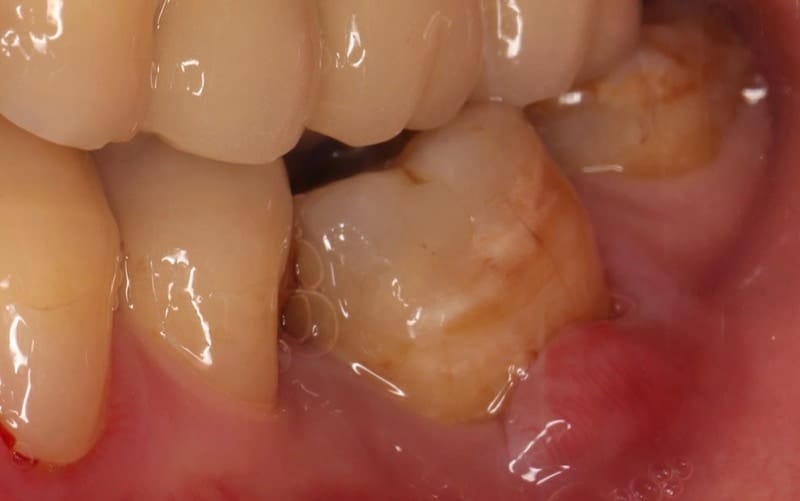

圖示:Mr.Lin左下臼齒牙齦近照,這顆牙齒同時有牙髓和牙周的問題

經過完整牙周病檢查後我們發現,全口牙周囊袋很多位置已經有5mm以上,齒槽骨平均流失大約30%,但有局部超過50%,並有缺牙五顆。值得注意的是,上方門牙假牙之間有縫隙,這其實是因為後牙缺牙造成『咬合崩壞』,合併牙周病牙齒鬆動,而產生牙齒位移的現象(病理性位移)。